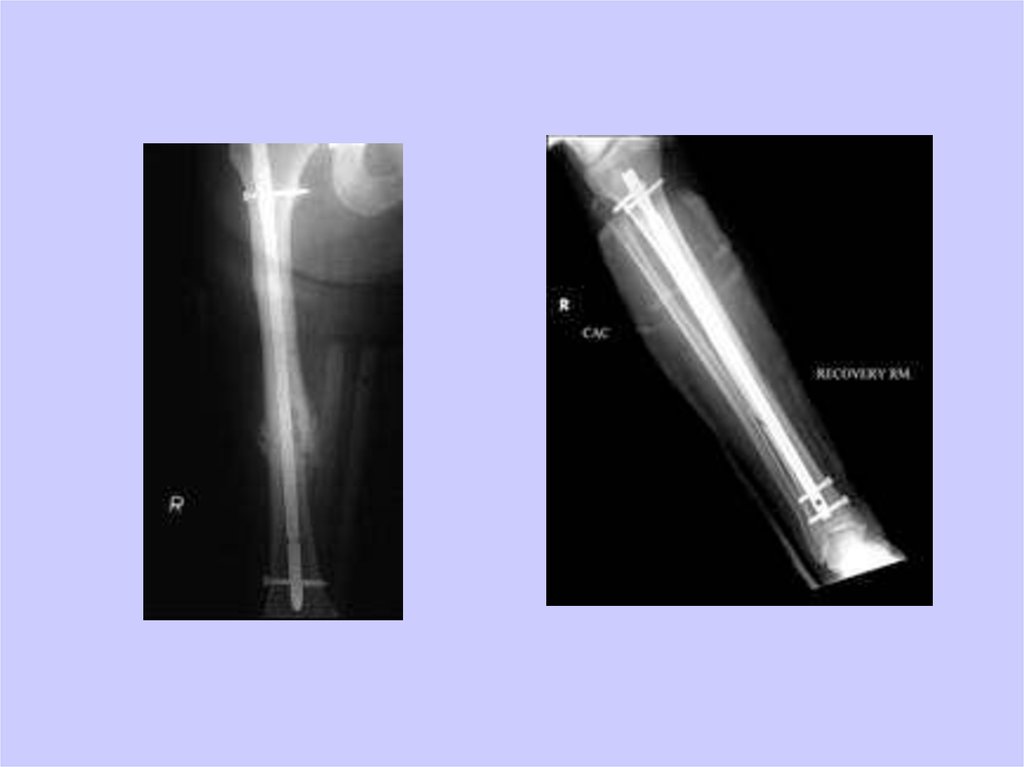

40. И еще раз репозиция

41. И еще раз репозиция

43. Внутренняя фиксация

• Внутрикостные стержни